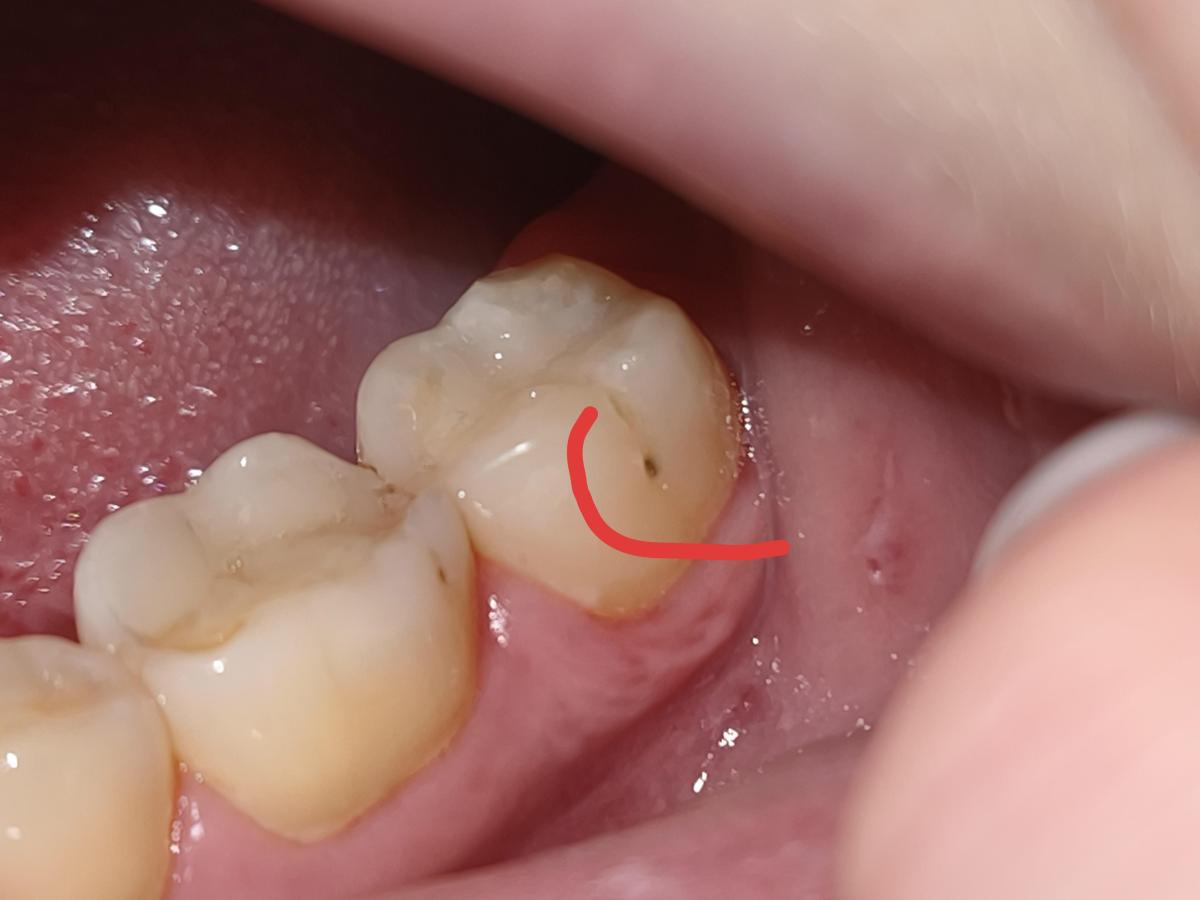

Вчера ходила лечить зуб. У этого стоматолога лечу не первый раз и все было хорошо. Сверху зуба доктор кариес убрал, его было много.

Когда пришла домой начала рассматривать и сбоку увидела что осталась дырочка, это не пятно, а прям углубление. Получается мне не долечили зуб ? Как такое возможно не заметить